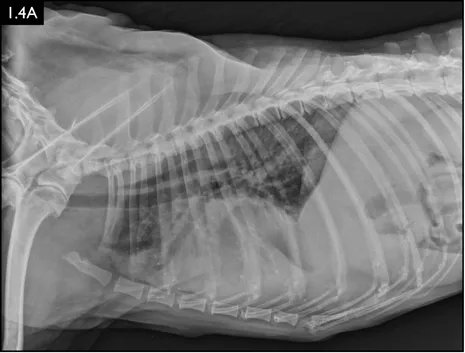

Diagnosis

Clinical signs can be strongly suggestive of bacterial pneumonia, but radiographs are important for confirmation, to characterize the disease (and potential etiology) and to provide a baseline for monitoring response to treatment (Figs. 1.4–1.6). A lag between clinical signs and radiographic changes can occur, and initial radiographs may be normal or appear discordant with clinical severity.

Fig. 1.4A–D Lateral and ventrodorsal radiographs of a dog with doxycycline-responsive pneumonia of unknown etiology before treatment ( A, B) and six days later ( C, D). Note the severe multilobar alveolar pattern that was present initially, most prominently in the left cranial lung lobe. (Courtesy of Atlantic Veterinary College)